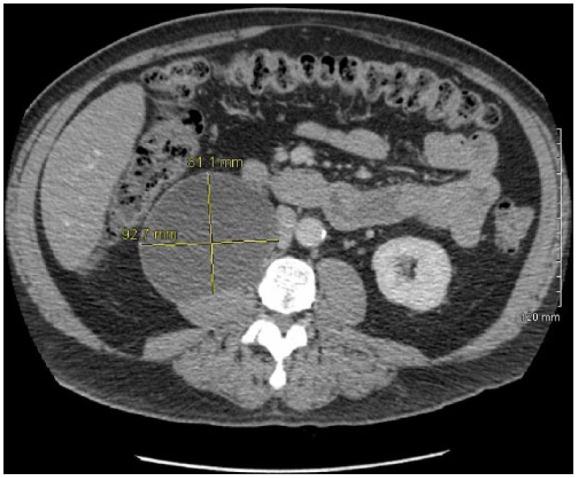

An incidental hypoechoic, solid appearing 8.2 × 7.6 × 7.8 cm mass arising off the inferior pole of the right kidney was found on abdominal ultrasound during evaluation for a history of alcoholism. Computerized tomography (CT) scan revealed small calcifications in the lower part of the cystic mass. Laparotomy with excision of the retroperitoneal mass was performed.

在对一名有酗酒史的患者进行腹部超声检查时,发现右肾下极有一个偶然发现的低回声、实性的8.2×7.6×7.8 cm肿块。计算机断层扫描(CT)显示囊性肿块下部有小钙化灶。进行了剖腹手术切除腹膜后肿块。